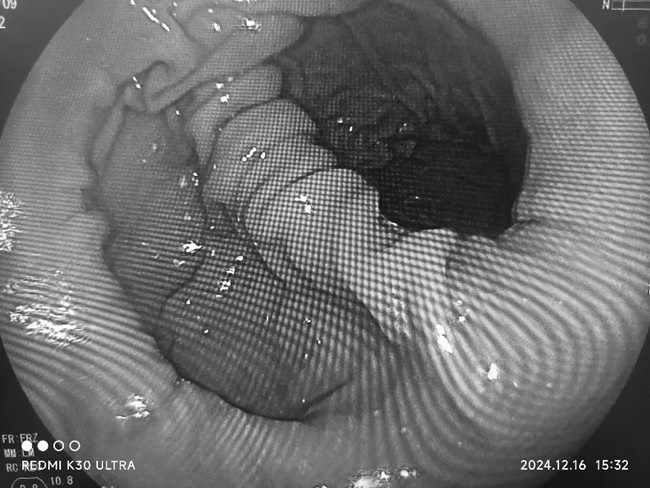

陈艳军主任经细致问诊、查体,并进一步完善胃镜检查,终于发现了症结所在,原来困扰她多年的根本不是“胃病”,而是她的胃“离家出走”了,高大娘被诊断为食管裂孔疝III型(混合型)。

Ⅲ型疝:是Ⅰ型和Ⅱ型的混合型疝,胃食管连接部和部分胃一起通过食管裂孔进入胸腔。